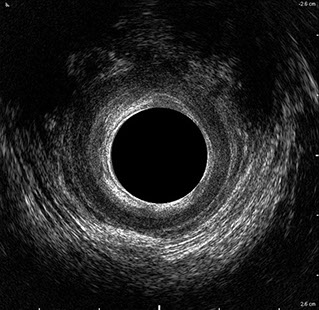

L’ecografia transanale è un esame diagnostico per immagini che consiste nell’introduzione di un trasduttore ad ultrasuoni. Le immagini qualitativamente migliori del canale anale sono ottenute usando un trasduttore rotante, montato in un manipolo rigido, che fornisce un’immagine a 360°. Con le apparecchiature più moderne è anche possibile ottenere immagini tridimensionali.

L’ecografia transanale permette di distinguere la sottomucosa che riveste il canale anale, lo sfintere anale interno, e lo sfintere anale esterno.

Le principali indicazioni all’esecuzione di tale esame sono lo studio dell’integrità delle strutture muscolari nei casi di incontinenza fecale, lo studio topografico dei processi settici perianali (ascessi e fistole) e lo studio dei processi proliferativi epiteliali (carcinoma anale).